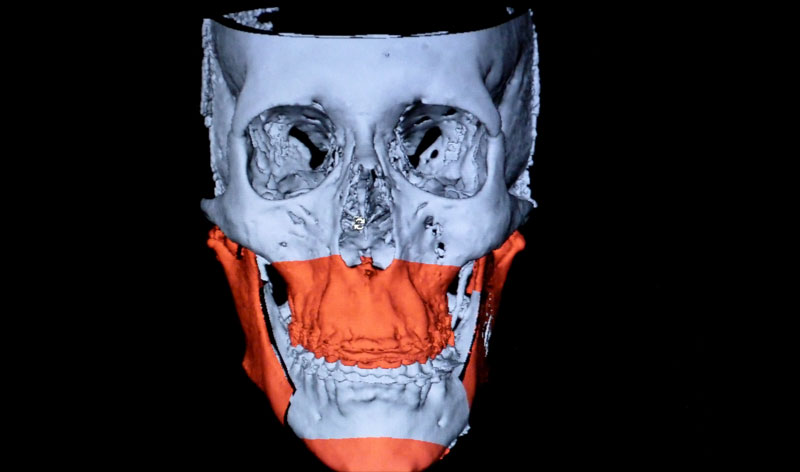

Imágenes comparativas en las que se aprecia el balance estético entre los dos tercios faciales, segundo tercio y tercer tercio. Se puede valorar cómo con las prótesis de malar se han logrado una mayor proyección del segundo tercio facial y, sobre todo, la corrección de esa imagen de depresión periorbitaria de la paciente. Además, al haber retruído la mandíbula, se ha conseguido ganar una mayor armonía facial y una mayor estética en la sonrisa.